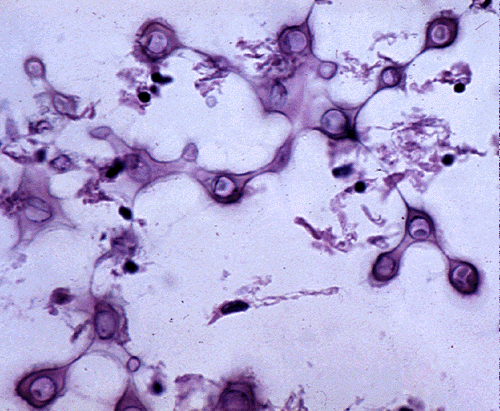

Cryptococcus is an oval yeast about the size of a red cell, surrounded by a gelatinous capsule. There are several species of cryptococcus. The most common, cryptococcus neoformans, causes 95% of infections. It is a worldwide fungus, present in bird droppings, vegetables, and soil. It may affect healthy individuals but is particularly common in immunodeficient patients, especially patients with HIV/AIDS. It is most often community-acquired. The portal of entry is the respiratory tract but pulmonary infection may be asymptomatic or minimally symptomatic. Cryptococcus spreads to the brain from the lungs and often causes meningitis without involving other organs. In the CNS, cryptococcus grows extensively in the subarachnoid space and perivascular spaces, which become cystically distended to the point that brain sections look like Swiss cheese. In immunosuppressed individuals, inflammation is absent or mild. In immunocompetent hosts, cryptococcus elicits a cell-mediated immune reaction with lymphocytes and epithelioid cell granulomas. Rarely cryptococcus may cause mass lesions (cryptococcomas). Cryptococcus meningitis has an insidious onset and may go on from weeks to years. It can cause hydrocephalus, dementia, cranial neuropathies and focal neurological deficits. The CSF in cryptococcosis shows mononuclear pleocytosis, elevated protein, and low glucose, similar to tuberculous meningitis. Yeasts can be identified by microscopy of the CSF and their antigens can be detected by latex agglutination.